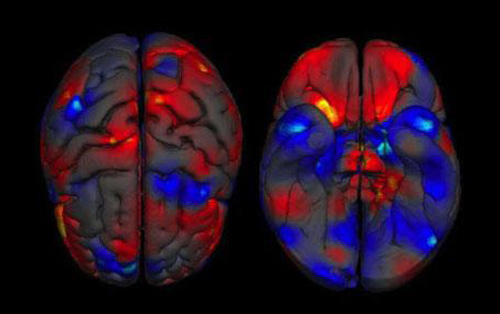

在这些图像里,女性(红色)具有更大容量的区域包括(b)右边下额回和中额回,额下回三角部和颞平面;(c)丘脑和右前扣带回;(f)左右丘脑;男性(蓝色)具有更大容量的区域,包括(c)带状前回;(d)双边后扣带回,楔前叶和左小脑;(e)前扣带回和后扣带回;(f)左右扁桃体,海马体和海马旁回。